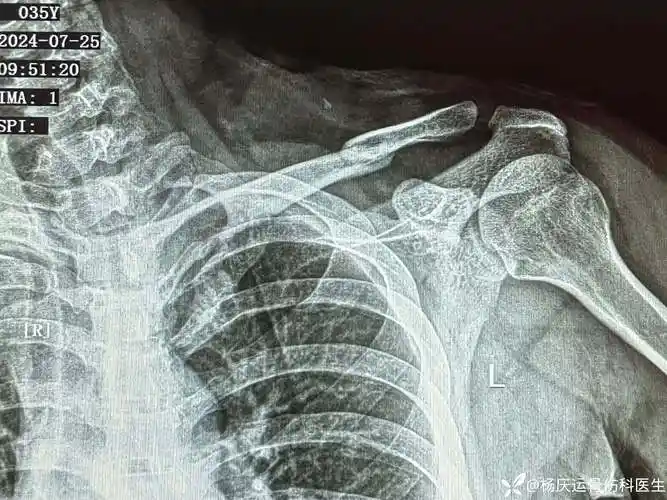

请专业老师看看我这个交通事故锁骨断裂骨折伤残能达到几级0517

iii度肩锁关节脱位是肩锁韧带,2条喙锁韧带(锥状韧带,斜方 - 抖音